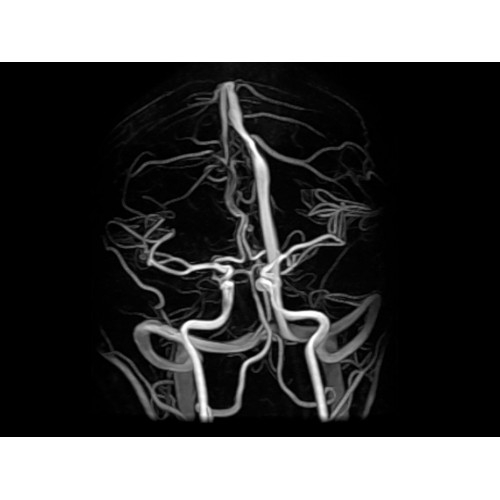

МР-ангиография Да